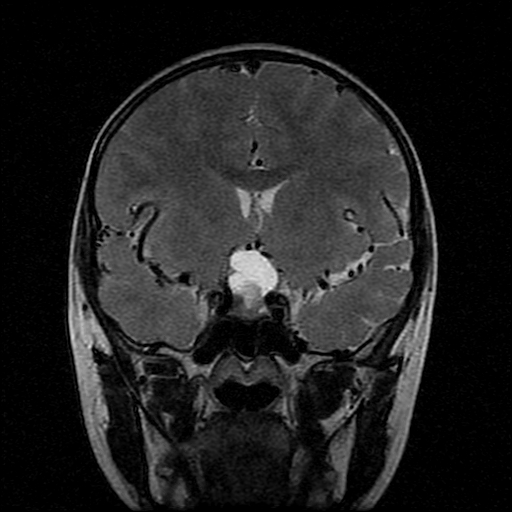

男性,12岁。反复头痛呕吐半月。脑积液无异常。病变部位ct值32hu,dwi无异常。

鞍上为主,累及鞍内,垂体受压位于鞍底。mri呈短t1、长t2信号,不太支持生殖细胞肿瘤,首考颅咽管瘤。

符合鞍上及鞍内颅咽管瘤影像表现,